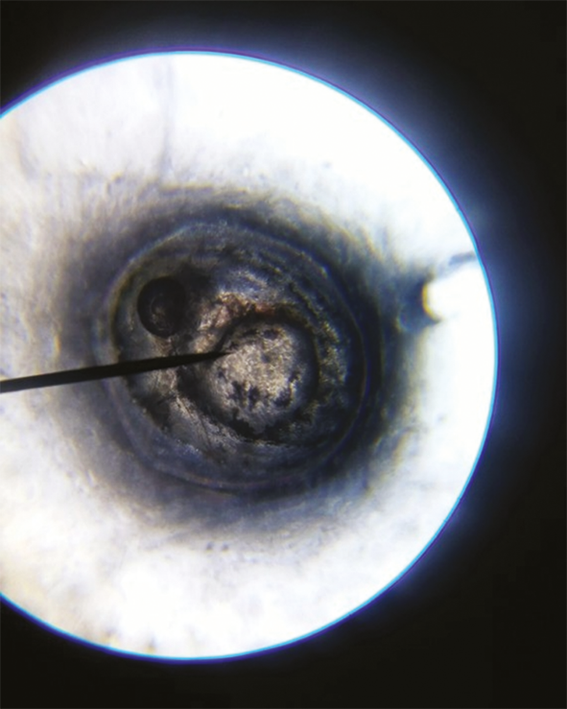

Как показали результаты исследования, на 1-е сутки в контроле кровообращение регистрировали у всех эмбрионов, а движение — лишь у 21,4 % (рис. 2). При исследовании нуклеоспермата натрия в дозе I кровообращение у эмбрионов регистрировали с частотой 37,5 %, а движение — с частотой 6,25 %. При исследовании нуклеоспермата натрия в дозе II кровообращение выявляли у всех эмбрионов, тогда как движение —только у 46,6 %. При исследовании препарата в дозе III кровообращение зафиксировано у всех эмбрионов, движение — у 18,75 %. На 3-и сутки добавляли новый параметр оценки жизнедеятельности эмбрионов (в некоторых случаях уже личинок Danio rerio) — появление на свет личинки, параметр «движение» оценивали по передвижению личинки по экспериментальной лунке, а не внутри икринки (рис. 3, 4). В контроле кровообращение зарегистрировано у 87,5 % эмбрионов, движения не наблюдали, появилось на свет 87,5 % личинок. При исследовании препарата в дозе I кровообращение определялось у 87,5 % эмбрионов, движения не наблюдали, на свет появилось 81,25 % личинок. При исследовании препарата в дозе II кровообращение наблюдали у 93,75 % эмбрионов, движение отсутствовало, на свет появилось 93,75 % личинок. При исследовании препарата в дозе III кровообращение наблюдали у 81,25 % эмбрионов, движение — у 37,5 %, на свет появилось 81,25 % личинок. Эксперимент на 4-е сутки показал, что в контроле кровообращение, движение и появление на свет были у 87,5 % эмбрионов. При исследовании препарата в дозе I кровообращение и движение регистрировали у 93,75 % эмбрионов, появление на свет — у 18,75 %. При исследовании препарата в дозе II все параметры составляли 93,75 %. При исследовании препарата в дозе III все параметры соответствовали 81,25 %. На 7-е сутки исследования все три параметра в каждой дозе сравняли свое значение: контроль — 87,5 % кровообращение, движение, появление на свет, доза I — 81,25 %, доза II — 93,75 %, доза III — 75 %. На 8-е сутки оценивали только активное передвижение личинки по экспериментальной лунке, так как все остальные показатели составляли 100 % для выживших эмбрионов. Эксперимент на 8-е сутки показал, что в контроле активно двигаются и удовлетворительно развиваются 37,5 % первоначально взятых живых эмбрионов, при введении нуклеоспермата натрия в дозе I — 50 %, в дозе II — 81,25 %, в дозе III — 75 % (рис. 5).

Fig. 2. Danio rerio embryo: day 1 of the experiment

Рис. 3. Эмбрион Danio rerio. Третьи сутки эксперимента

Fig. 3. Danio rerio embryo: day 3 of the experiment

Рис. 4. Личинка Danio rerio. Третьи сутки эксперимента

Fig. 4. Danio rerio larva: day 3 of the experiment